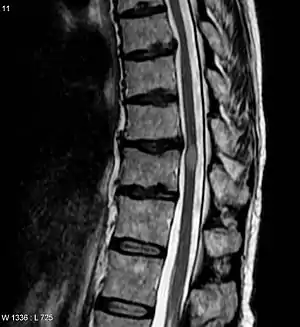

| تصویر اسکن امآرآی که نشاندهنده ضایعه میلیت عرضی است (این عارضه با رنگ روشنتر، بیضی شکل در میانه-راست تصویر)، این اسکن سه ماه پس از بهبود بیمار گرفته شدهاست. | |